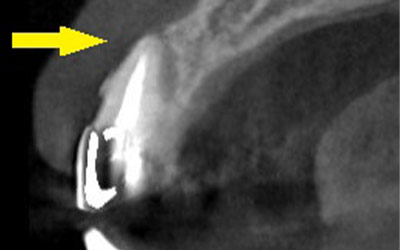

写真は初診時の患者様のレントゲン写真です。左右とも、上顎第一大臼歯を失っていました。通常のレントゲン写真では、骨量が十分かと思われましたが、CTを撮影してみると、黄色の矢印部位、左側では、少し骨の高さが足りませんでした。

CTを撮影して、測定すると、右側はギリギリ10mmぐらいの高さで、左側は6mmほどしかありませんでした。

そこで、左側はソケットリフトを併用して行いました。インプラント埋入手術後のCT、黄色の矢印部分、インプラント周囲にドーム状に補填材が白く写り、インプラントがしっかりと埋入できています。